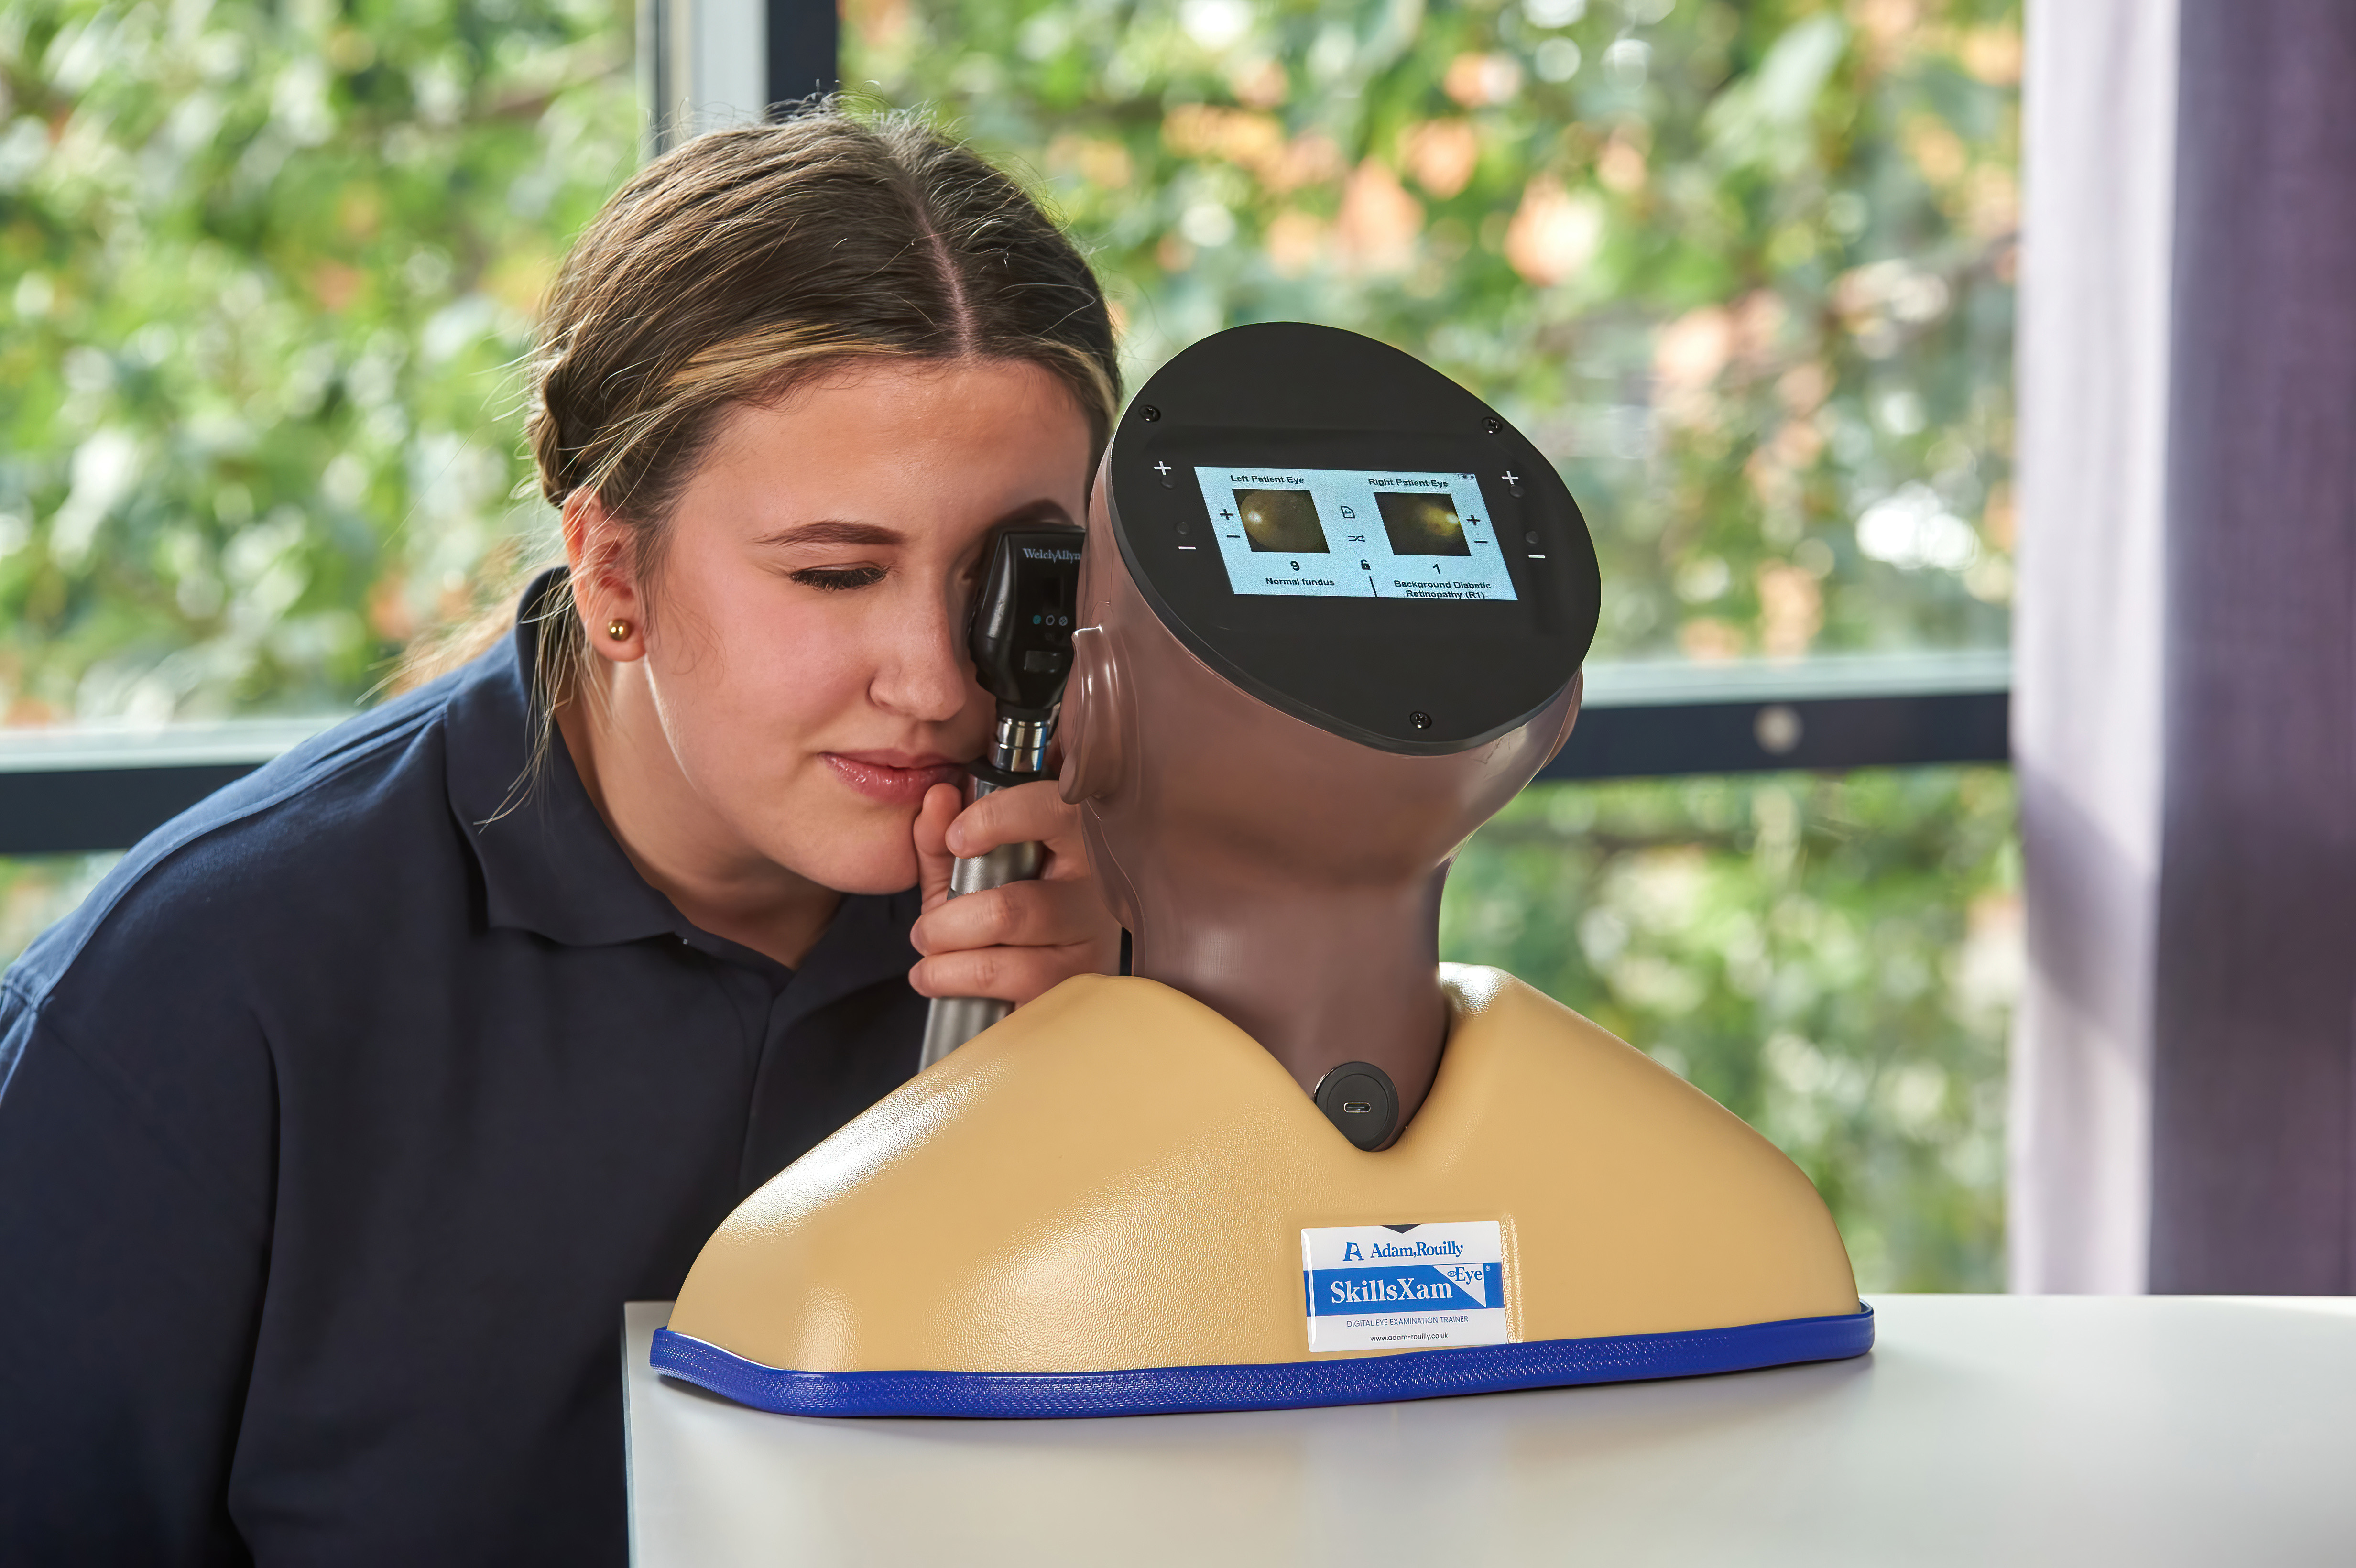

Developed in collaboration with Professor Vinod Patel, Professor, Diabetes and Clinical Skills, the Enhanced Digital Eye Examination Trainer takes ophthalmoscopy training to a new level of realism and inclusivity.

For the first time, advanced digital technology allows trainees to experience how the same eye condition can present differently in patients with light and dark skin tones. In darker-skinned patients, deeper pigmentation in the fundus reduces vessel visibility, a nuance replicated only in the AR503/50 Dark model. This provides learners with invaluable exposure to the clinical variations they will encounter in real practice, enhancing both competence and confidence. Offering two product versions enables trainees to gain an awareness of these visible variances.

Inside the model, conditions are displayed with greater clarity and true-to-life colour on high-resolution circular LCD screens. A 4.3-inch external touchscreen interface makes operation intuitive and effective, allowing users to preview, search, and select conditions or build customisable sets for teaching, self-directed learning, or examination scenarios.

The Enhanced Digital Eye Examination Trainer delivers an authentic, adaptive, and inclusive learning experience, redefining the standard in ophthalmoscopy training.